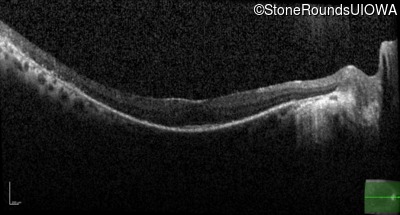

Optical Coherence Tomography - Left - 20/20 -2

Exemplar / OCT Stack

OCT Stack